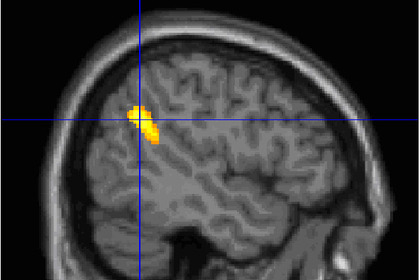

Оказалось, что у тех, кто хорошо помнит сны, в двух областях коры мозга наблюдается повышенная спонтанная активность. Эта активность отличает таких людей и во сне, и наяву. Первая из обнаруженных томографией областей относится к средней префронтальной коре (mPFC) — этот отдел связан с высшими функциями мозга, такими как принятие решений и абстрактное мышление. Вторая активная область относится к участку, соединяющему теменную и височную кору; ранее было показано, что его работа связана с концентрацией внимания. Интересно, что у пациентов с повреждением обеих этих областей мозга наблюдалось резкое снижение памяти на сновидения.